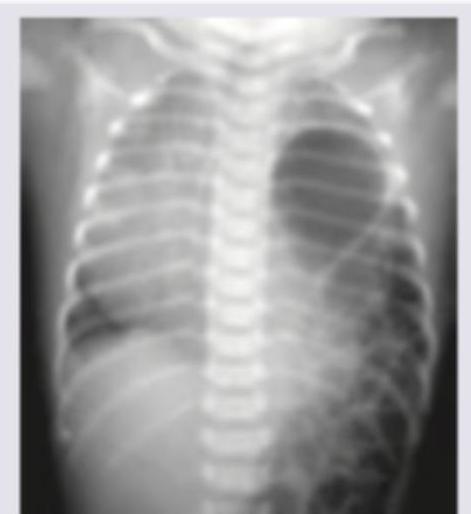

A newborn presents with respiratory distress shortly after birth. The chest X-ray shows bowel loops in the thoracic cavity and absence of bowel loops in the abdominal area. There is associated hypoplasia of the ipsilateral lung. What is the most likely diagnosis?

Explanation: ***Congenital diaphragmatic hernia*** - The presence of **bowel loops in the thorax** and their **absence in the abdominal cavity** are classic radiological signs of congenital diaphragmatic hernia (CDH). - This condition occurs due to a **defect in the diaphragm** (most commonly posterolateral Bochdalek hernia), allowing abdominal contents to herniate into the thoracic cavity. - CDH is often associated with **pulmonary hypoplasia** of the ipsilateral lung due to compression by herniated abdominal contents during fetal lung development. - **Management:** Immediate respiratory support, surgical repair after stabilization. *Bowel loops in thorax* - This describes a **radiological finding**, not a diagnosis. - While this finding is present in CDH, it does not represent the underlying pathology or condition. *Absence of bowel loops in abdominal area* - This also describes a **radiological finding** resulting from displacement of abdominal organs into the chest. - It is a consequence of the hernia, not the diagnosis itself. *Lung hypoplasia* - This describes a **complication/consequence** of CDH, specifically the underdevelopment of the lungs. - While strongly associated with severe cases and contributes to mortality, it is not the primary diagnosis but rather a major complication that determines prognosis.

Explanation: ***Most common associated defect is Pulmonary hypoplasia*** *(FALSE statement - correct answer for "except" question)* - **Pulmonary hypoplasia** is a direct consequence of CDH caused by compression from herniated abdominal contents, not an "associated defect." - True **associated defects** include **cardiovascular anomalies** (20-30% of cases), **chromosomal abnormalities**, and other congenital malformations. *Pulmonary artery hypertension is most important factor determining survival* *(TRUE statement)* - **Pulmonary hypertension** and its impact on **right ventricular function** are indeed the critical determinants of survival in CDH. - The elevated **pulmonary vascular resistance** leads to right-to-left shunting, exacerbating hypoxemia and determining prognosis. *Posterolateral left sided defect is the most common site* *(TRUE statement)* - **Left-sided Bochdalek hernias** (posterolateral defects) account for approximately **80-85%** of all CDH cases. - The chest X-ray shows bowel loops in the left hemithorax, confirming this typical presentation. *Scaphoid abdomen occurs due to herniation of contents into chest cavity* *(TRUE statement)* - **Scaphoid abdomen** is a classic clinical finding in severe CDH due to extensive herniation of abdominal contents. - The abdomen appears distinctly **sunken** because organs like stomach, intestines, and liver have herniated into the chest cavity.